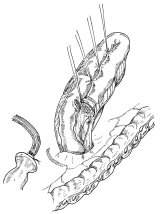

壁細胞。休止状態と分泌状態

どこかの国際学会でスライドに使っていただいたようです。確か一枚目を描くのに5時間、二枚目が3時間かかりました。